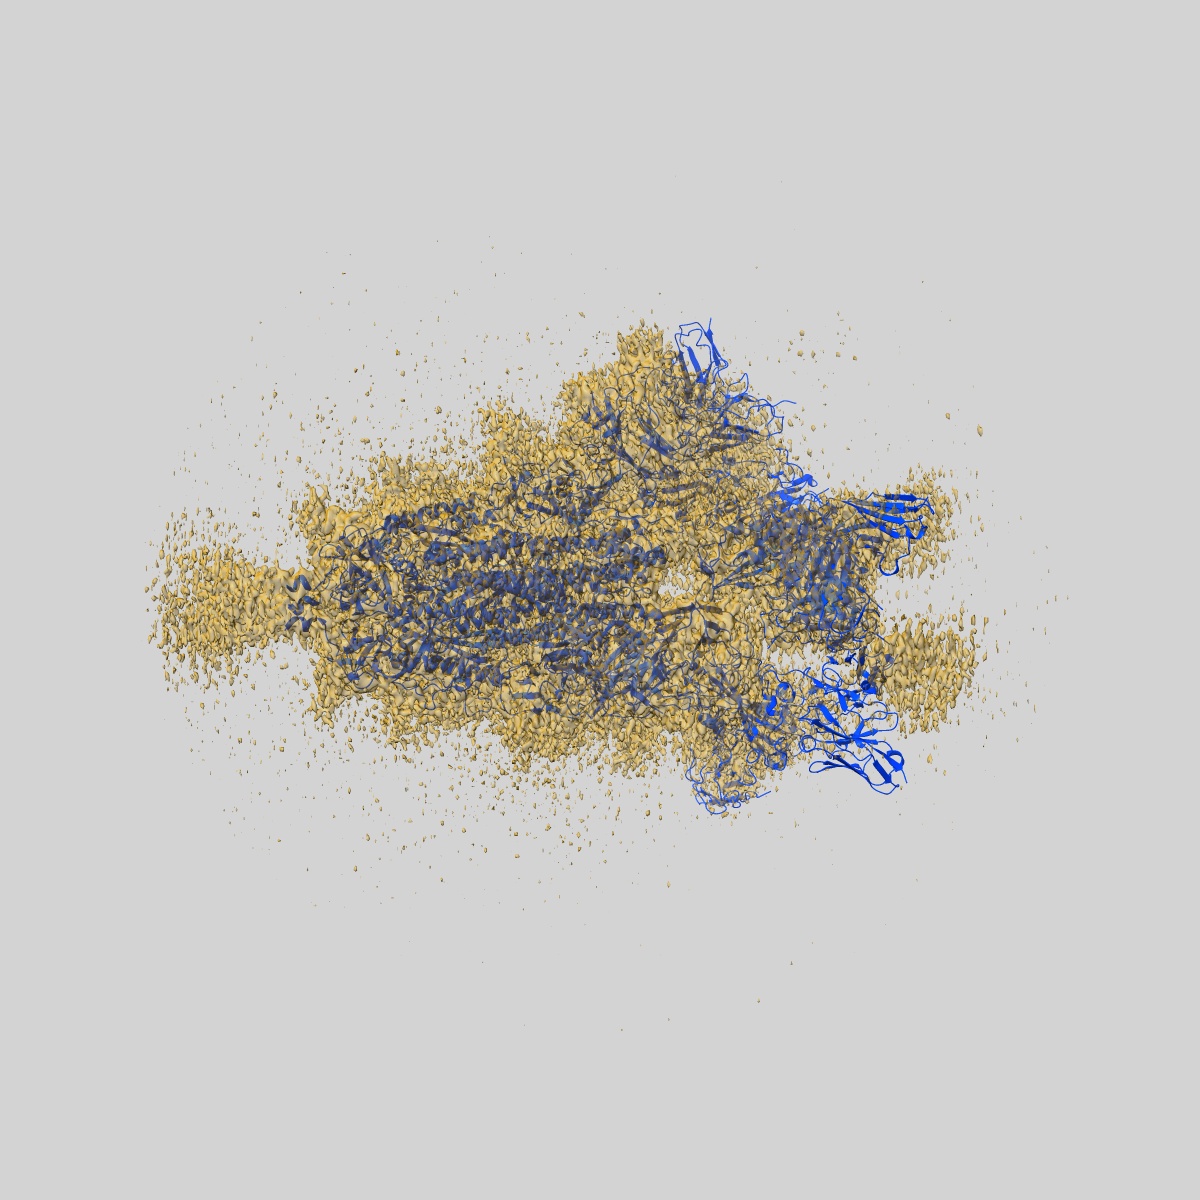

Cryo-EM structure of SARS-CoV-2 Omicron spike glycoprotein in complex with three F61 Fab and three D2 Fab

Single-particle3.04 Å

Sample: SARS-CoV-2 Omicron spike in complex with F61 and D2 Fab

Fitted models: 7xst

Structural basis of a two-antibody cocktail exhibiting highly potent and broadly neutralizing activities against SARS-CoV-2 variants including diverse Omicron sublineages.